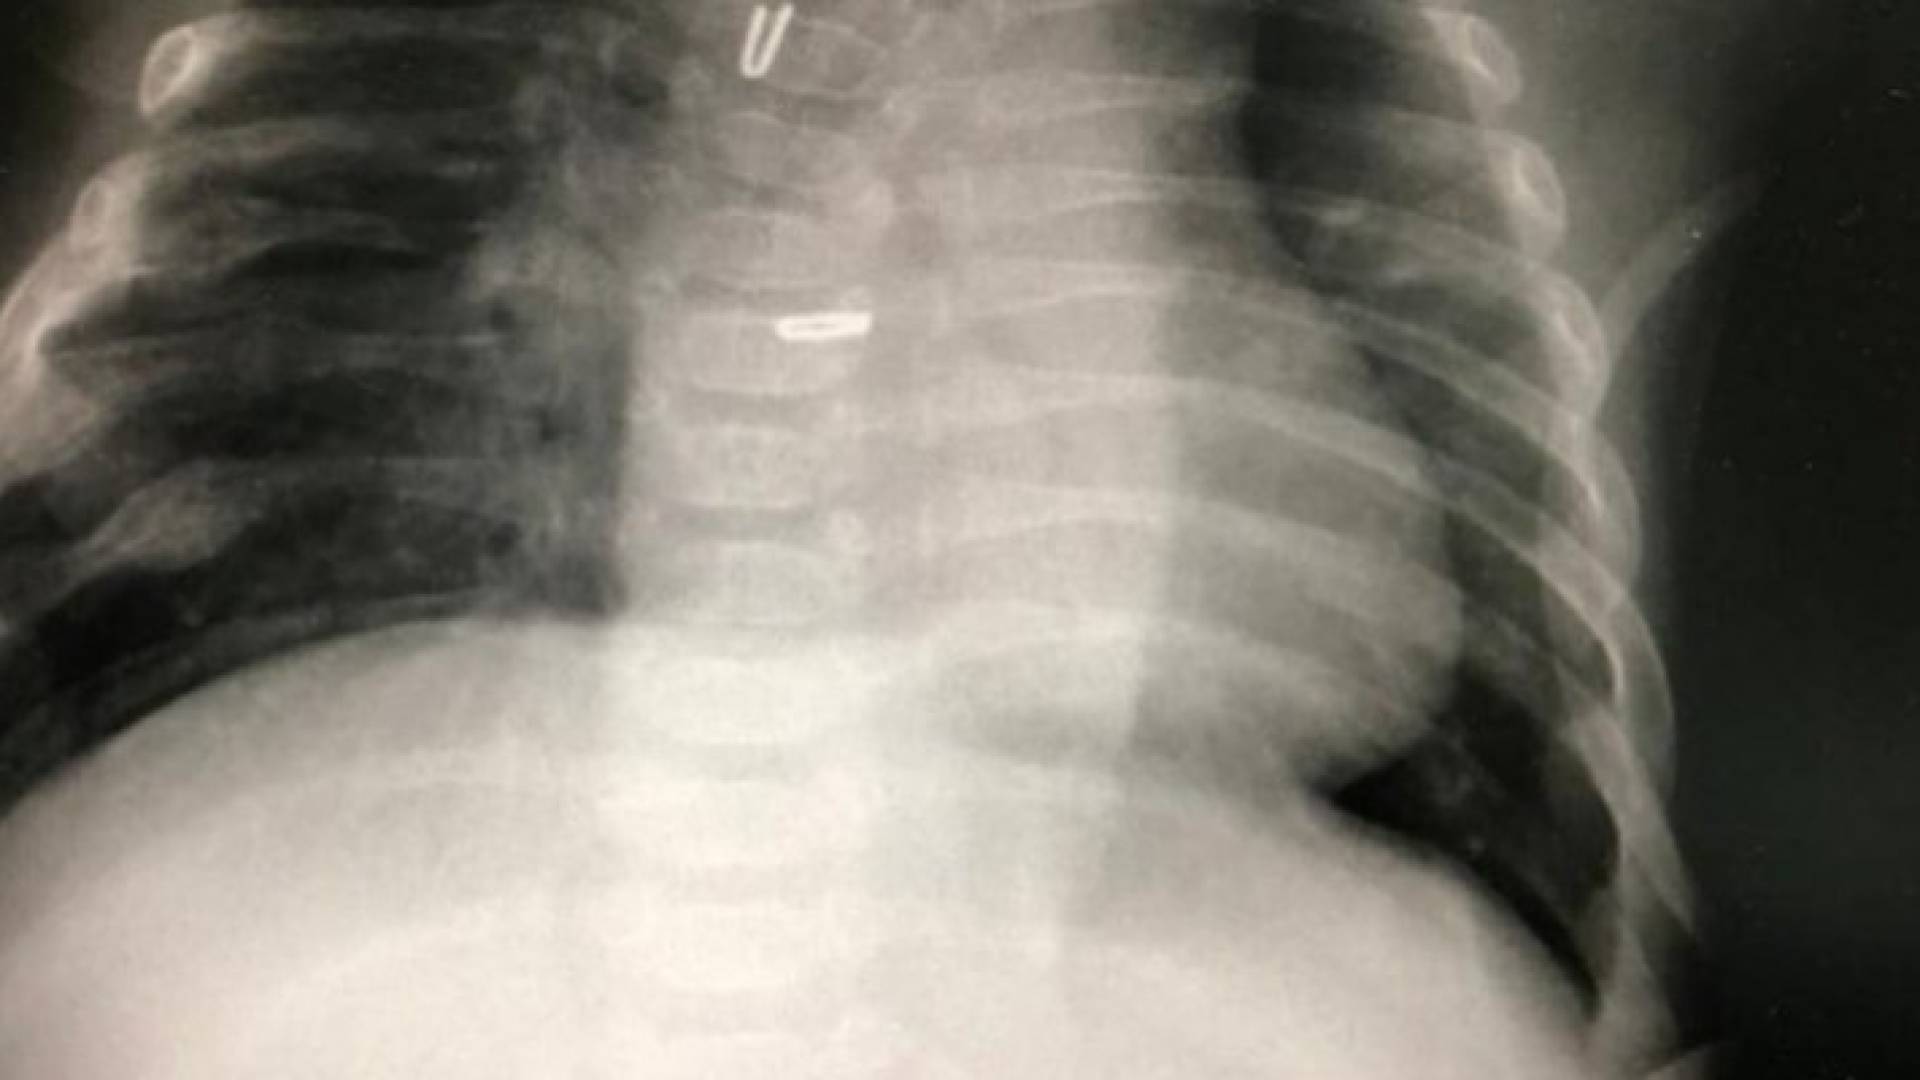

In a statement Sunday, JUH said that the operation was carried out using a laparoscope in the first stage, when the infant was just two days old, and then the upper and lower extremities of the esophagus were tightened using modern technology that is inserted into the chest cavity.

This process made the esophagus connect naturally six weeks later in a successful manner.